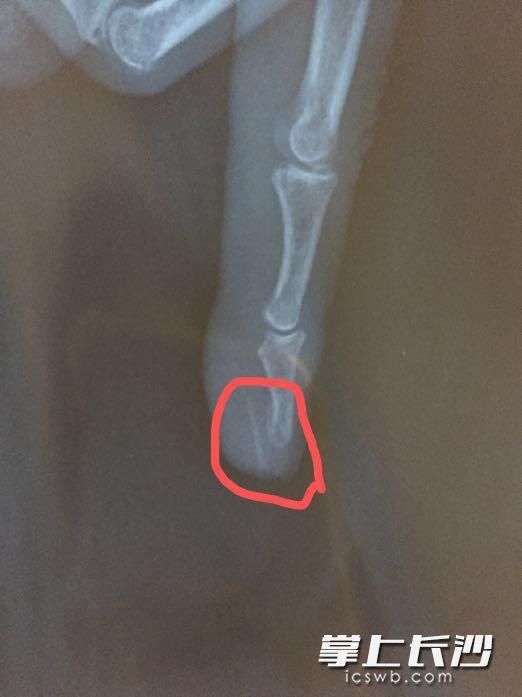

经过X射线检查,骨科主治医师王冶发现曹大妈肿胀的食指内有一根长约2厘米的针状物。“哎呀,肯定是一根鱼刺,半年前扎进去的鱼刺!”曹大妈恍然大悟。